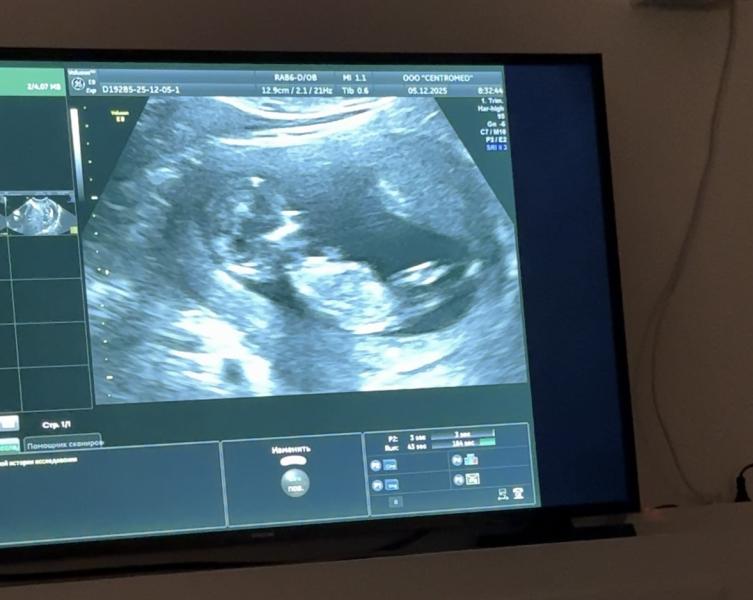

Как определить пол ребёнка по УЗИ: половой бугорок и другие признаки

Ким курдугуй 🩷🩵?😅половой бугорокпут костубэтэх бьлх

На первом фото как девочка, на втором мальчик )

На 12 недель не понятно,тоже долго разгадывала кто😁17 недель уьу точно покажет

Девочка кажется

Девочка бьлах)

Уол курдук😍